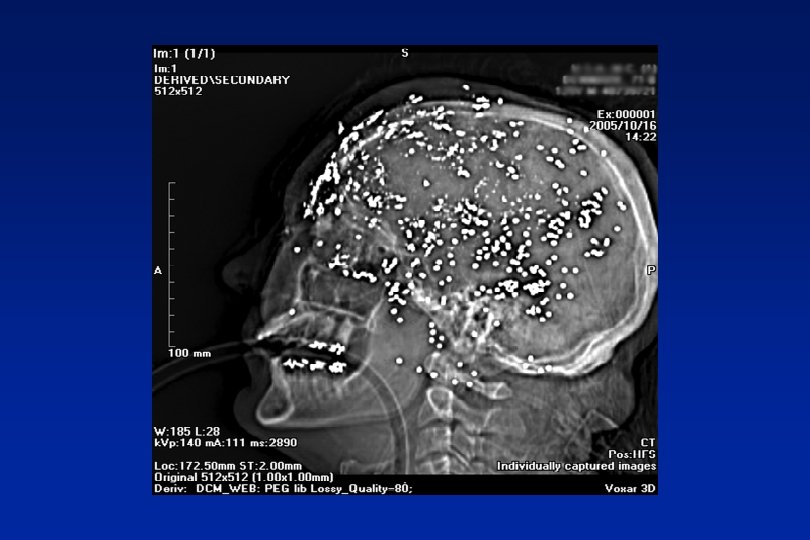

Space occupying lesions Stretch, compression, blockage n Benign – cysts, A-V malformations n Malignant – primary secondary

Red Flags n Abnormal neurological symptoms or signs n History of cancer elsewhere

Orange Flags n Aggregated by Valsalva manoeuvre n Headache with significant change in character n Awakes from sleep n New headache over 50 years n Memory loss n Personality change